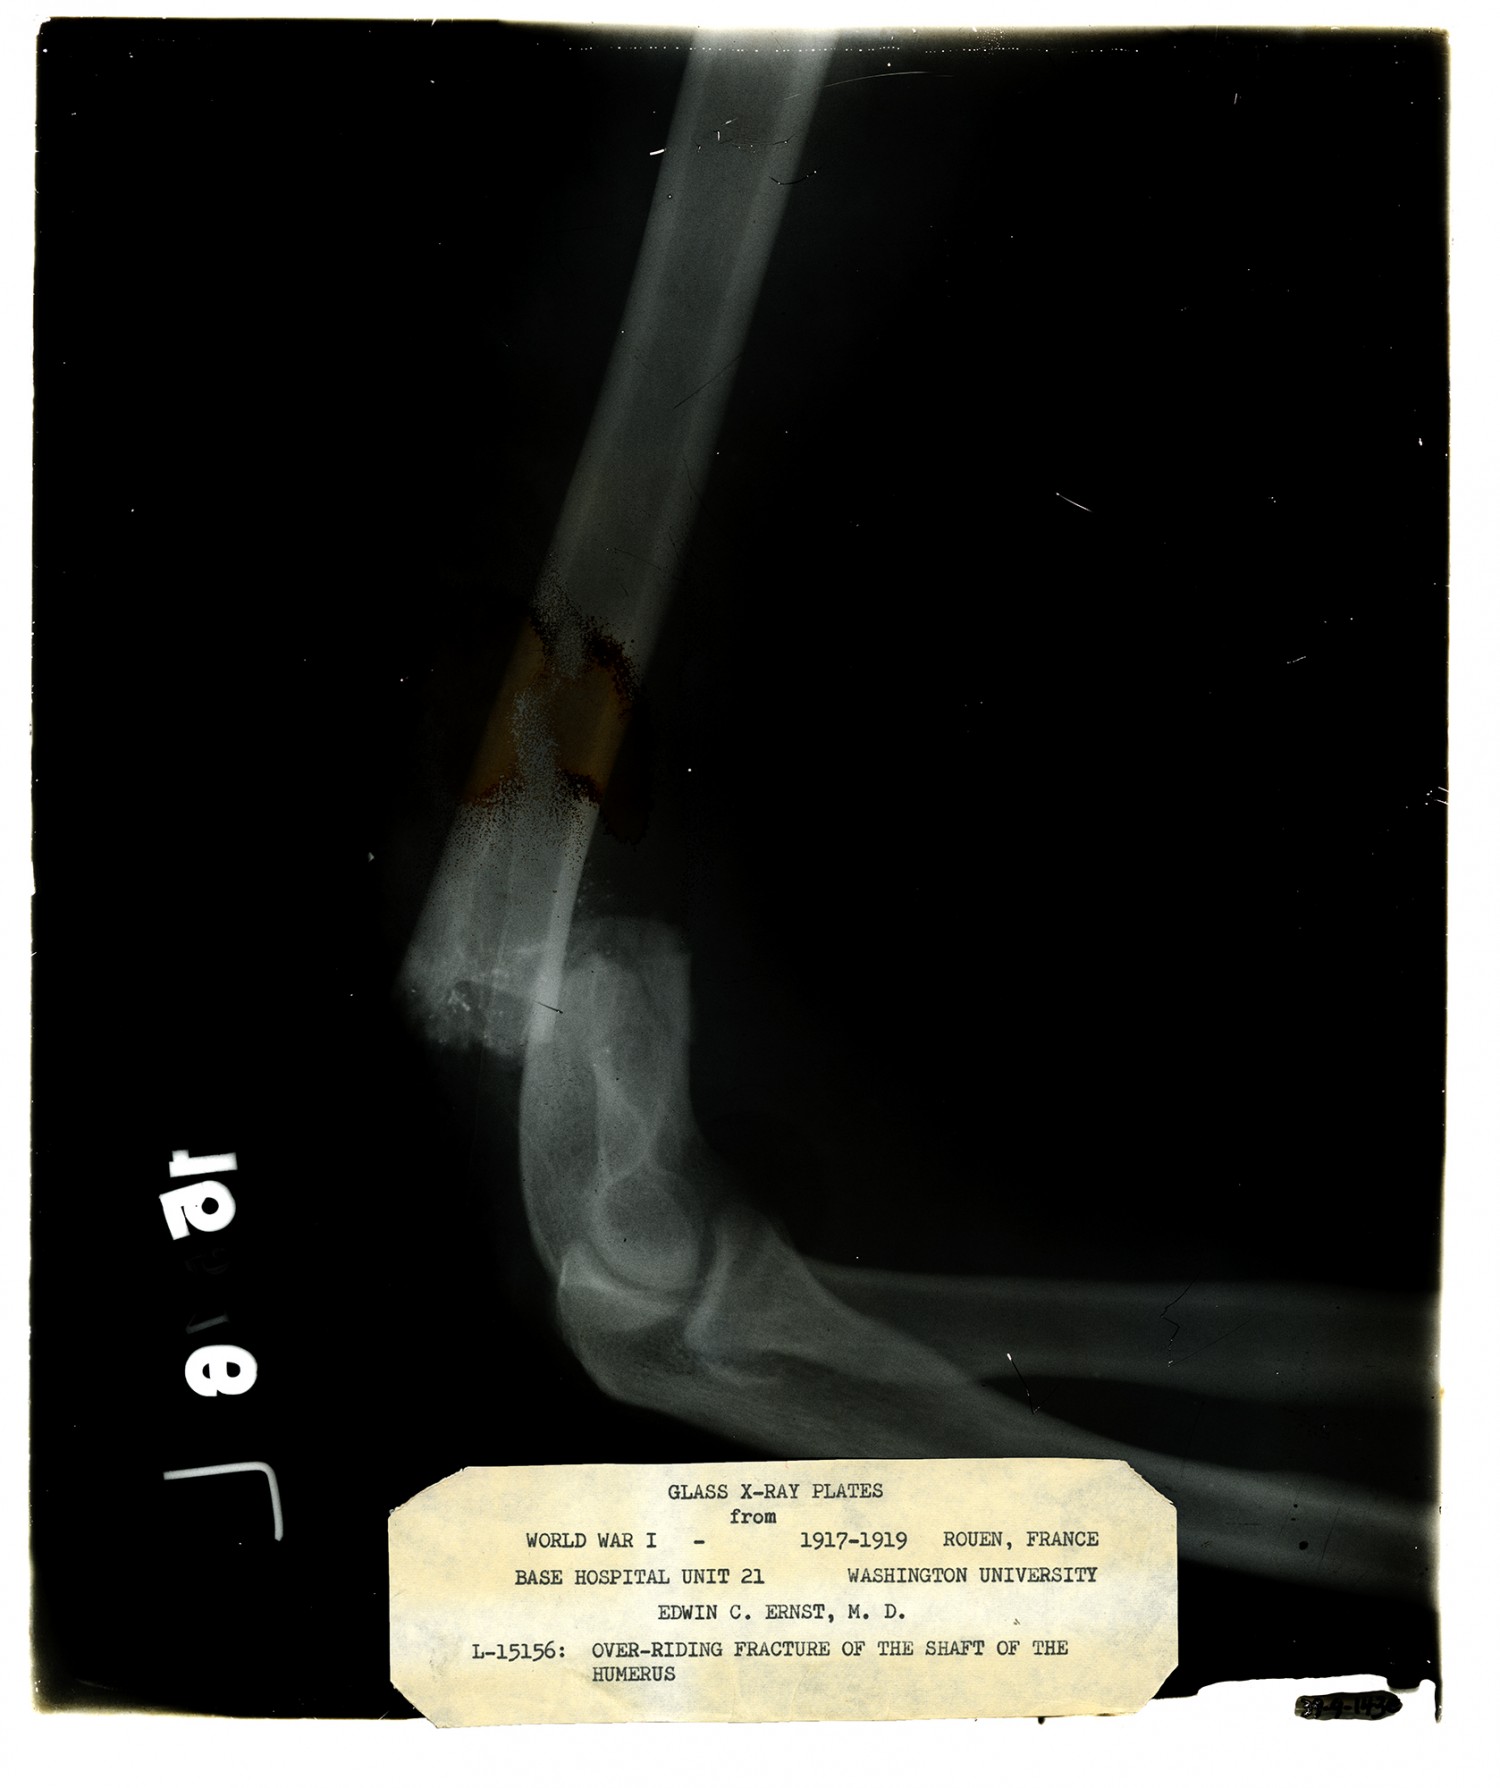

GLASS X-RAY PLATES from WORLD WAR I - 1917-1919 ROUEN, FRANCE BASE HOSPITAL UNIT 21 WASHINGTON UNIVERSITY EDWIN C. ERNST, M. D. L-15156: OVER-RIDING FRACTURE OF THE SHAFT OF THE HUMERUS

| Description | X-ray taken by Edwin C. Ernst of Base Hospital 21 in Rouen, France of an over-riding fracture of the shaft of the humerus. Base hospital 21 was formed from faculty and students from Washington University School of Medicine. Ernst designed his own portable x-ray equipment to help quickly diagnose injured soldiers. |